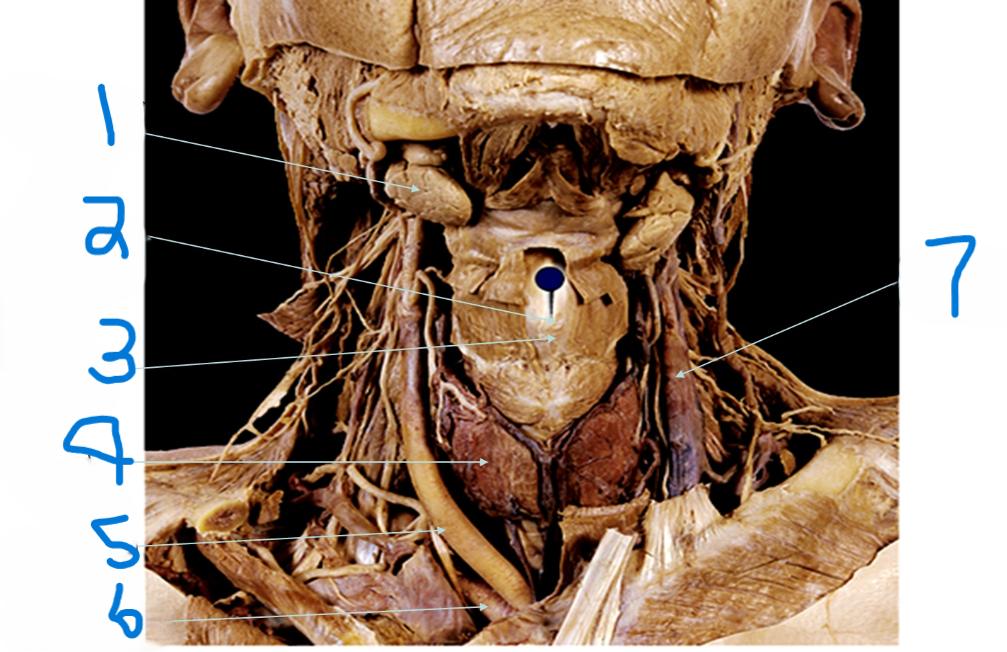

What is depicted by #1

Laryngeal Prominence (adams apple)

What is depicted by #2

Thyroid cartilage

What is depicted by #3

Thyroid gland

What is depicted by #4

Right common carotid artery

What is depicted by #5

Right subclavia artery

What is depicted by #6

Left internal jugular vein

What is depicted by #7